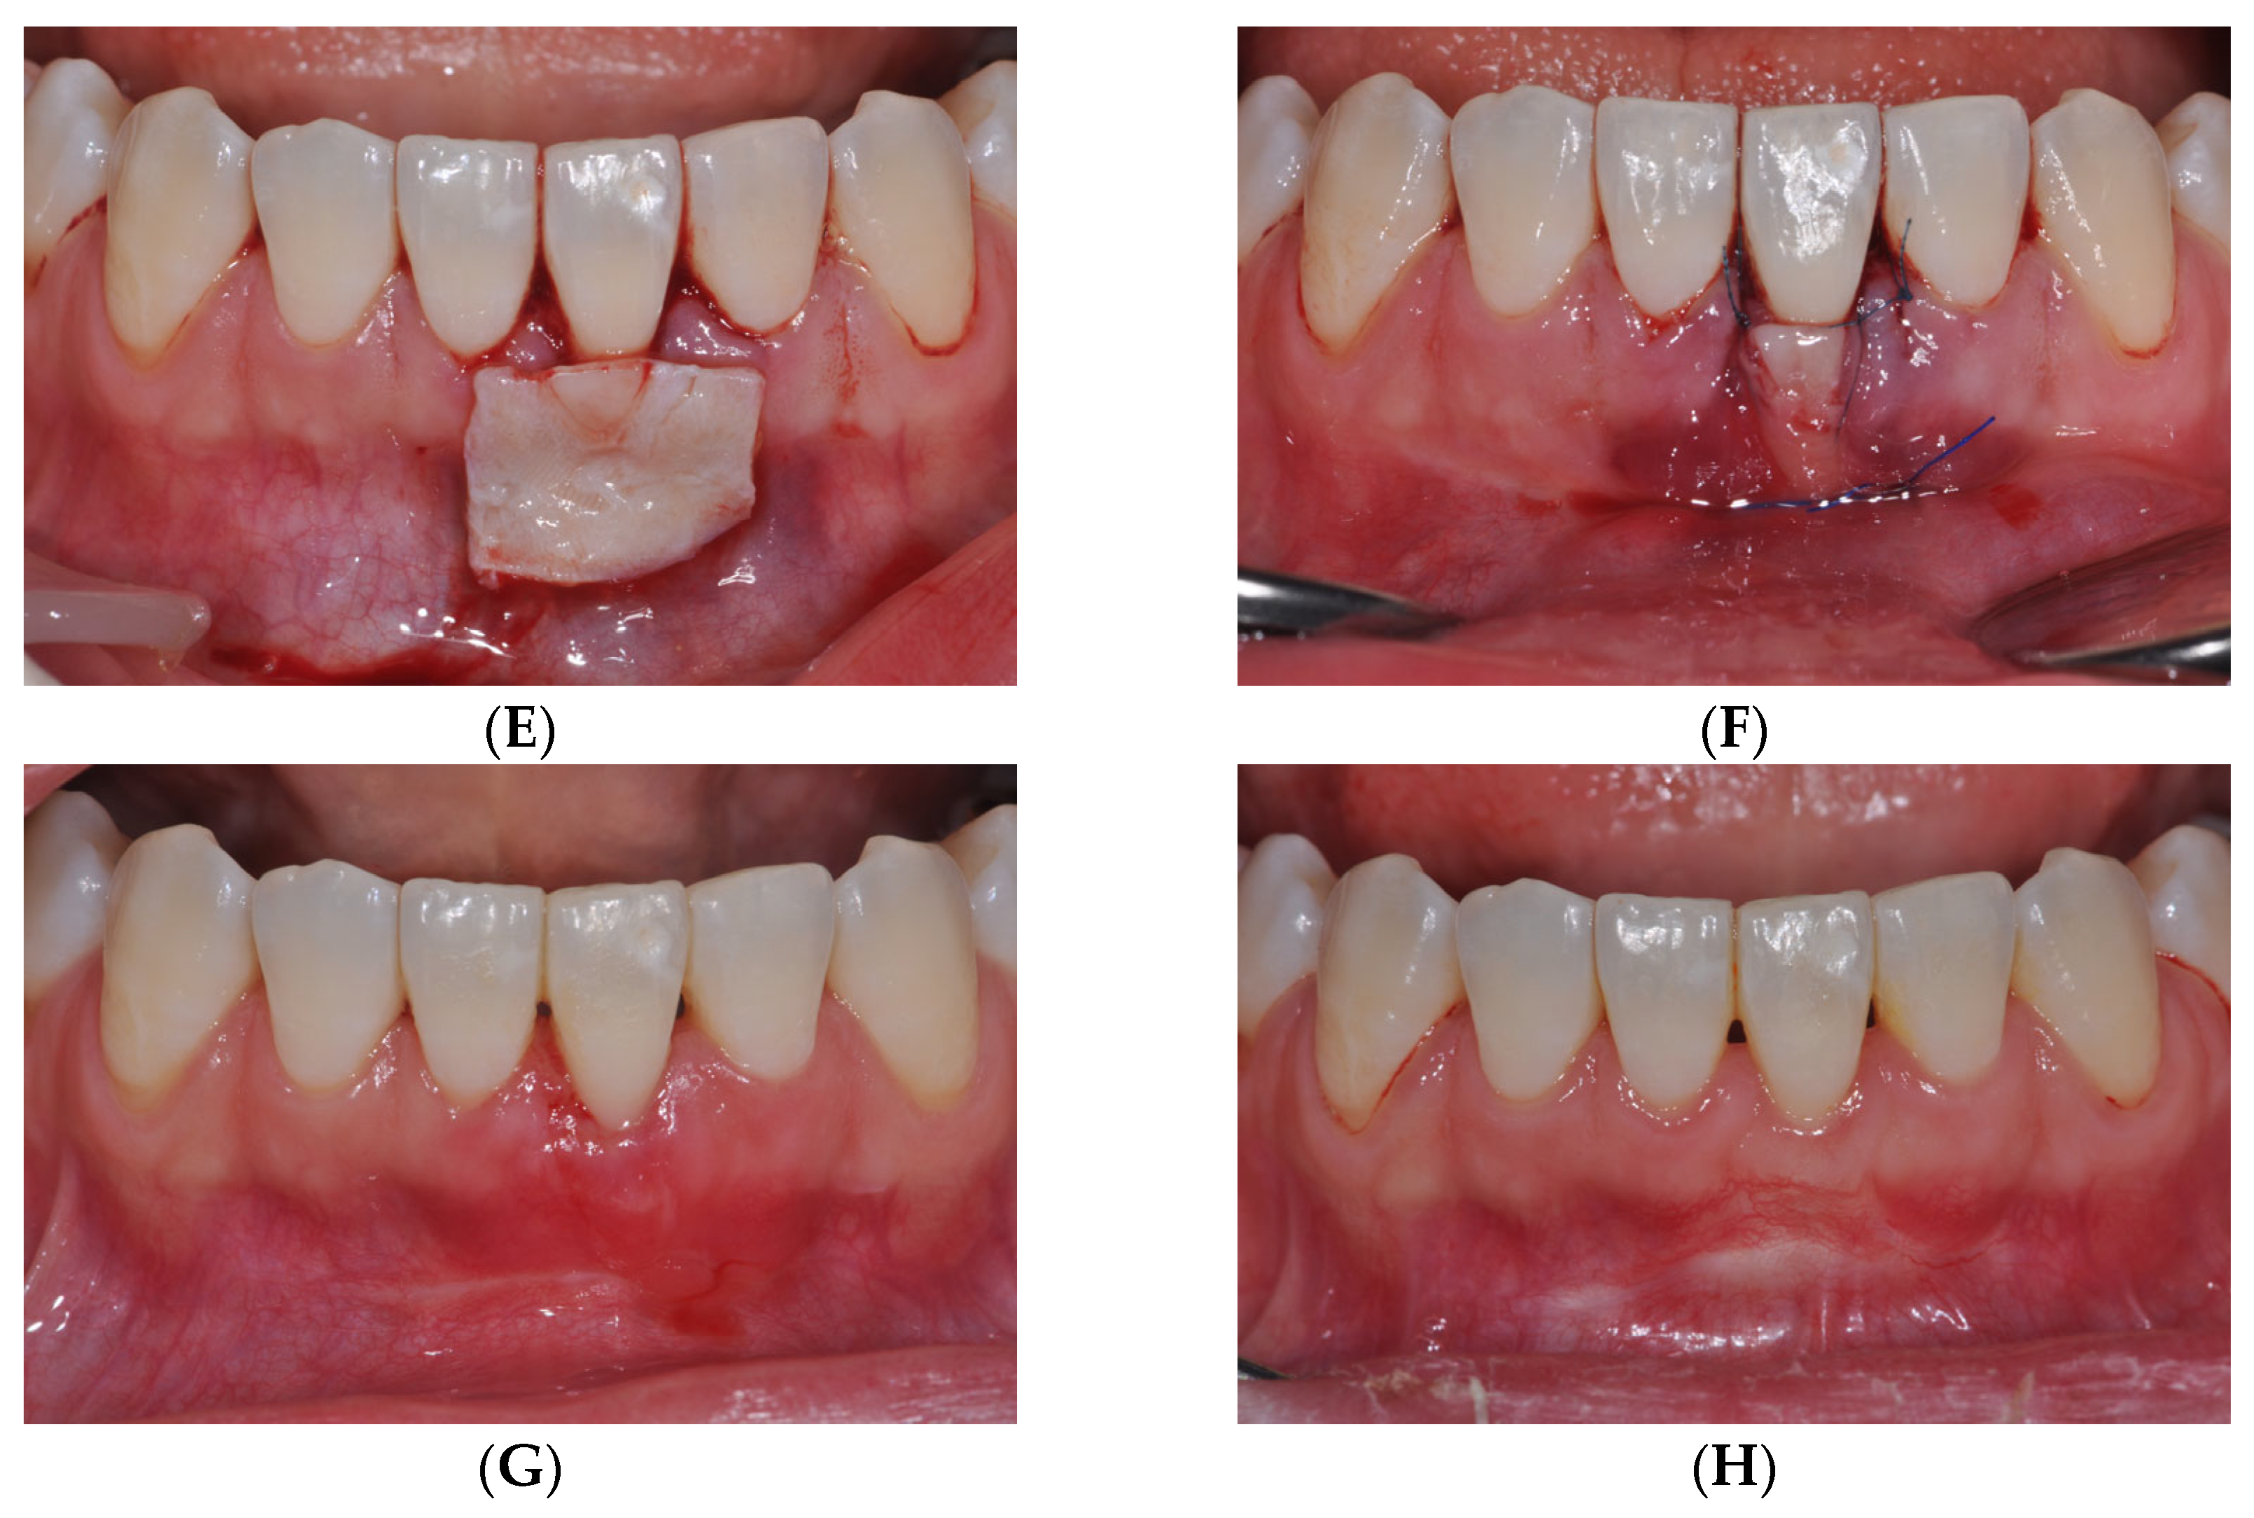

2.2.1. tPECTG

2.2.2. vPECTG